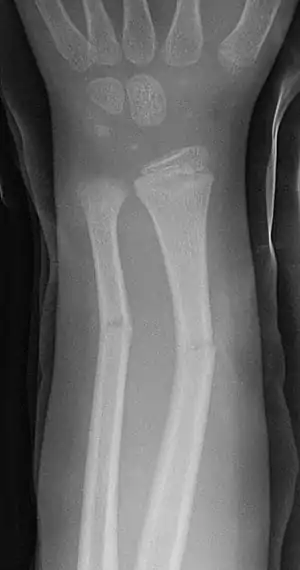

| Greenstick fractures on X-ray. | |

A greenstick fracture is a fracture in a young, soft bone in which the bone bends and breaks. Greenstick fractures occur most often during infancy and childhood when bones are soft. The name is by analogy with green (i.e., fresh) wood which similarly breaks on the outside when bent.

The greenstick fracture pattern occurs as a result of bending forces. Activities with a high risk of falling are risk factors. Non-accidental injury more commonly causes spiral (twisting) fractures but a blow on the forearm or shin could cause a greenstick fracture. The fracture usually occurs in children and teens because their bones are flexible, unlike adults whose more brittle bones usually break.